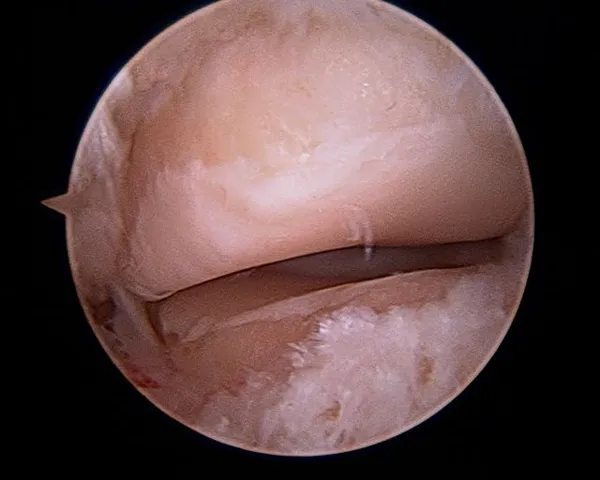

Cleaning out the joint

Scar tissue around the Posterior facet